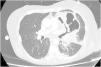

A 63-year-old woman arrived to the Emergency department with cyanosis, severe hypoxia and septic shock. We decided to orotracheal intubation and ICU admission. In the first hours in-ICU, she evolved with worsening of shock, severe refractory hypoxemia, and hypercapnia, without response to prone position, for which she decided to implement support with V-V ECMO, and allow-us to perform a lung CT Scan (Fig. 1) and a bronchoalveolar lavage. Among findings a voluminous abscess communicating with the distal airway indicative of bronchopleural fistula (Fig. 2). In the respiratory cultures, were isolated: Haemophilus influenzae, and Parvomonas micra. Based on these results, we optimized antibiotic therapy. In the following days, envolved with notable improvement, decrease in Noradrenaline until withdrawal. Progressive reduce V-V ECMO parameters until weaning at 12th day. A tracheostomy was performed to wean her from mechanical ventilation. The patient was finally discharged to ward.